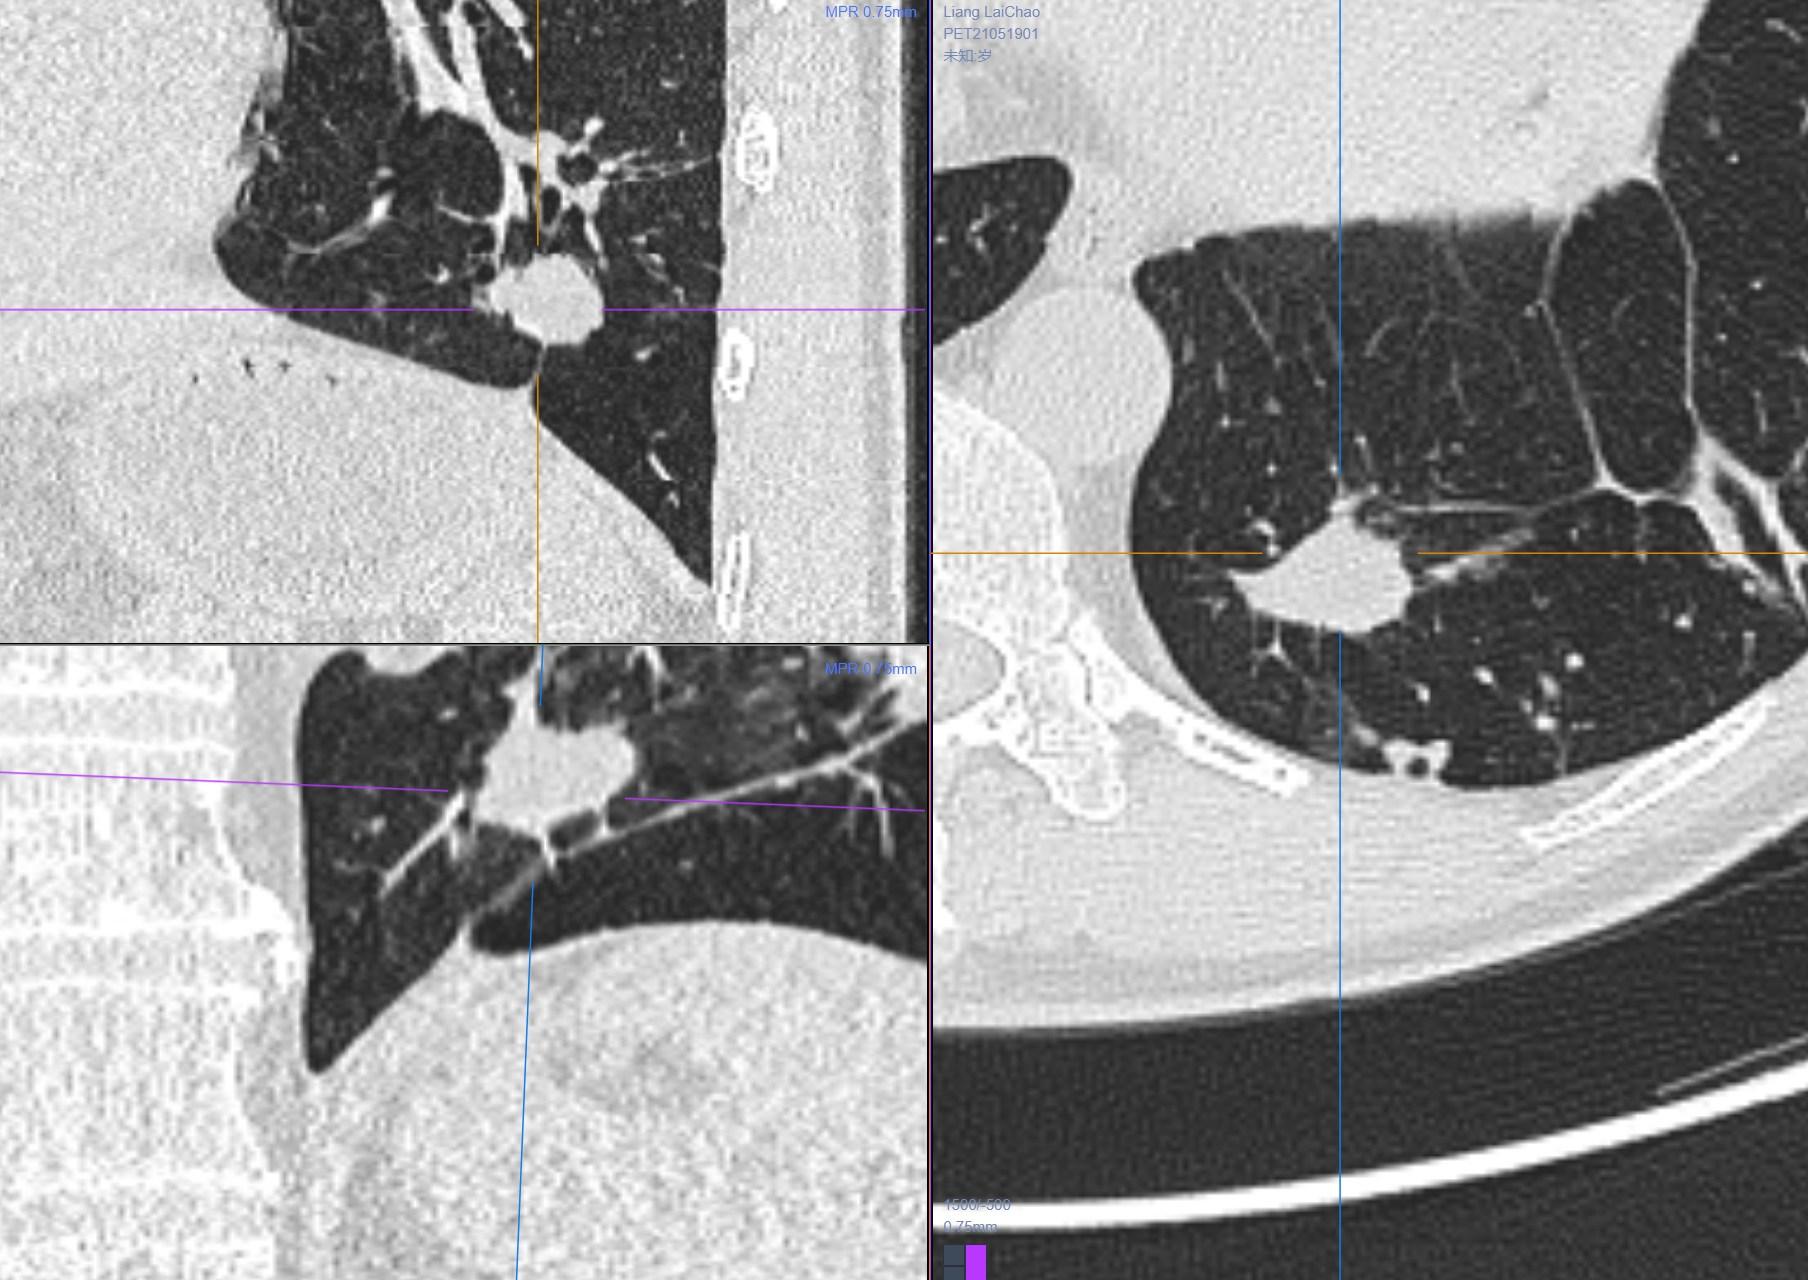

4.男性 53岁 以脑梗塞灶入院,发现内内3cm大软组织肿块。

没有什么能够阻挡我对这个病灶的诊断,考虑为肉芽肿性病变。

病理: